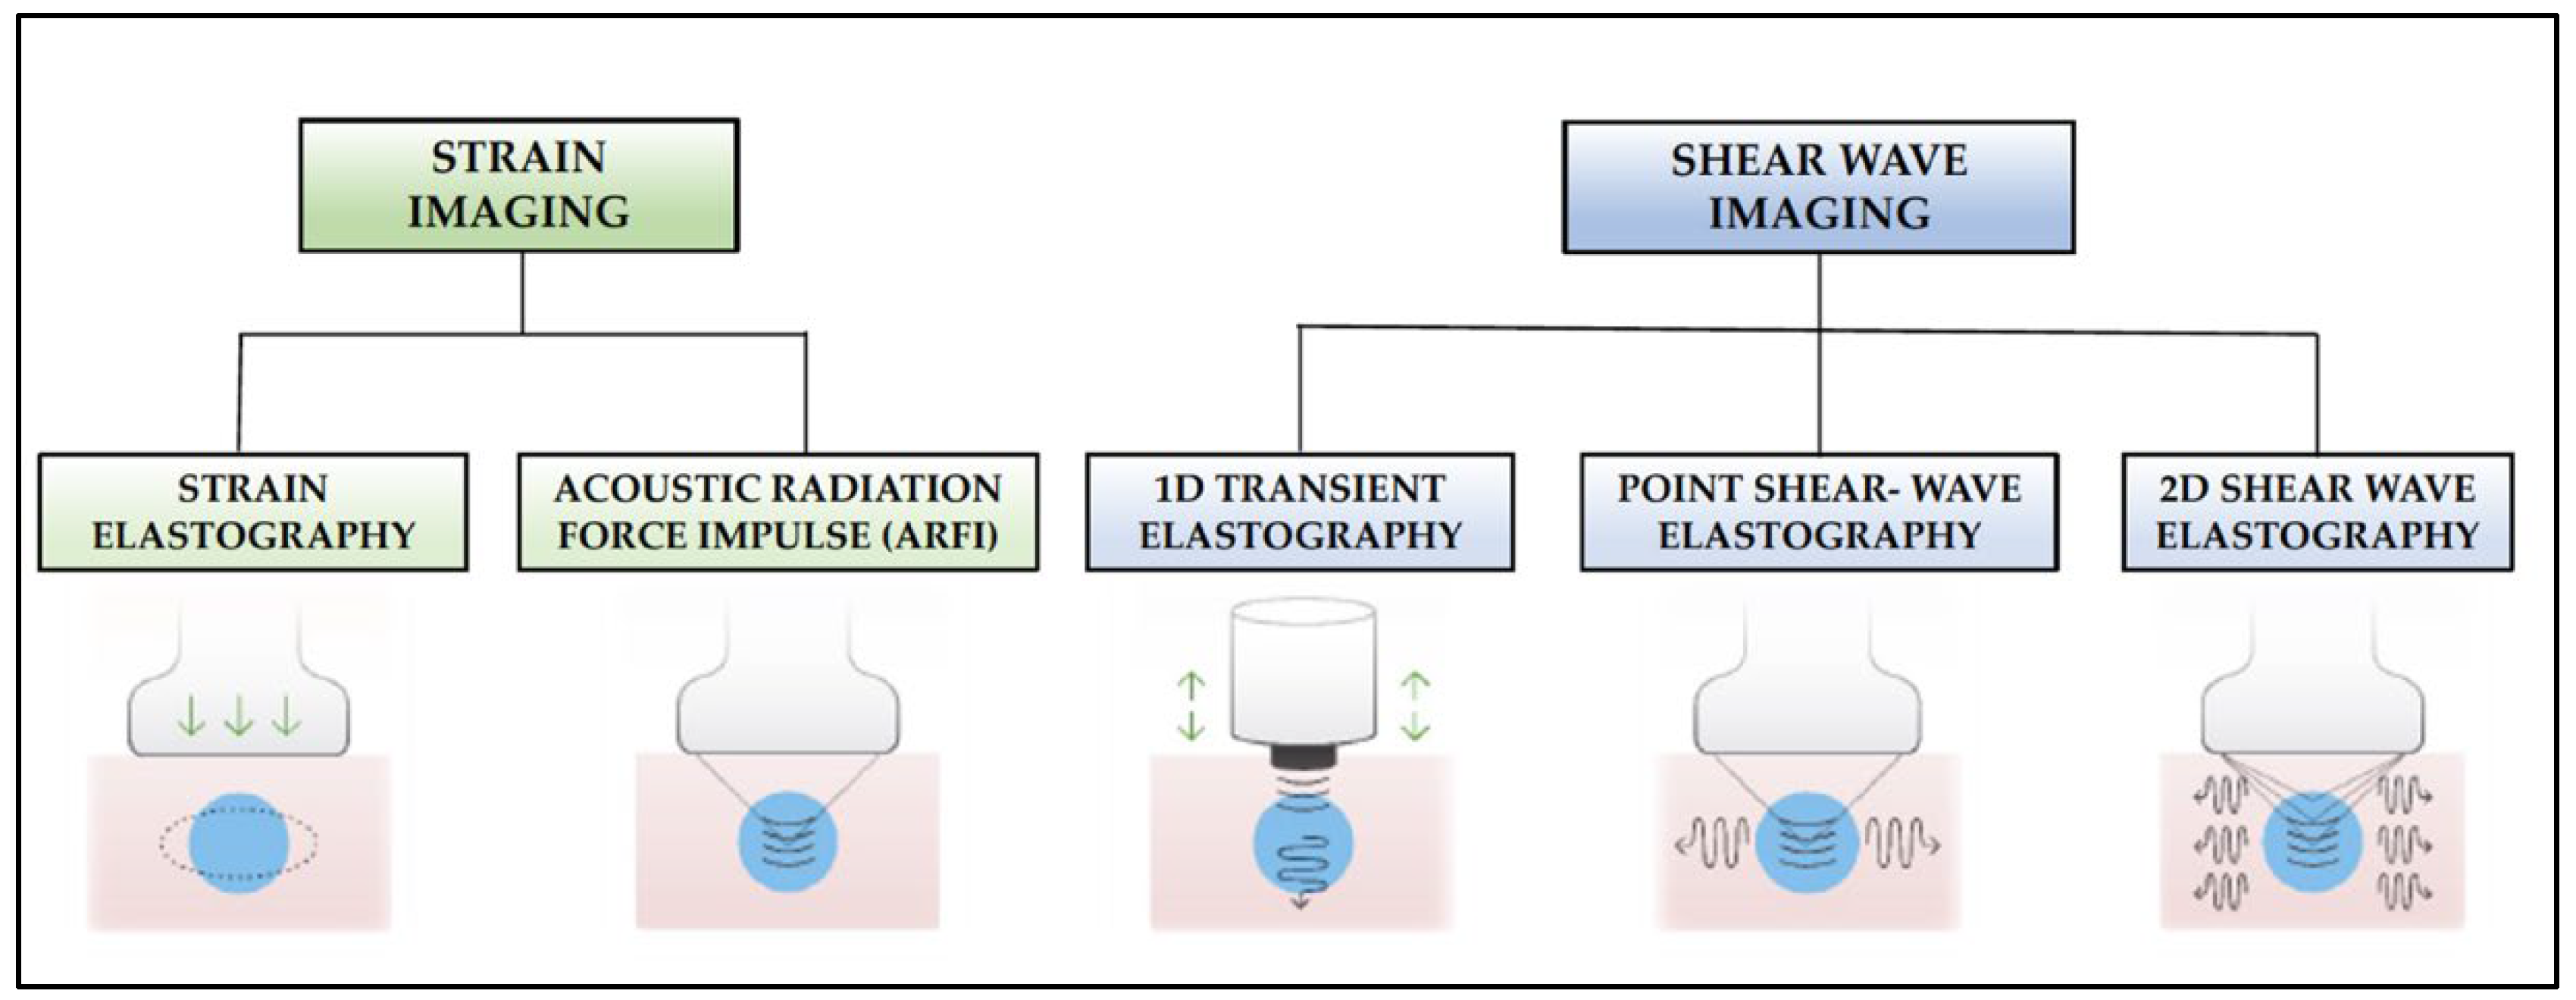

- Strain elastography: Depending on the type of stimulation, there are different strain elastography modalities. There are modes that require gentle compression with the transducer by the examiner, and other modes where pressure is generated by physiological movements of the patient, such as breathing. Whatever the mode of stimulation, there is a displacement of the tissue in the same direction as the pulse. This displacement (strain measurement) is recorded by the device as an indirect measure of tissue elasticity and plotted on a color map called an elastogram.

- Acoustic Radiation Force Impulse (ARFI): Focused acoustic radiation pulses of short duration (0.1–0.5 ms) achieve tissue displacement in the same direction as the impulse, i.e., perpendicular to the skin surface. As a result, the generated waves are captured and displayed on a greyscale elasticity map, where the brightest areas correspond to those with the highest elasticity (soft tissues) and the darkest areas to those with the lowest elasticity (hard tissues). Thus, it does not require manual external compression and it provides a one-dimensional measure of tissue elasticity on a measurement area that can be positioned in a B-mode image plane.

- 1D-Transient elastography (FibroscanTM): This is based on the generation of an external vibration (50 Hz) that is transmitted from the body surface to the target tissue, where compression is produced. The speed of transmission of the resulting shear waves, which is proportional to the stiffness of the tissue, is then recorded (expressed in kPa). It is used mostly for the assessment of liver fibrosis in chronic liver disease (assessment of a tissue volume of 1 cm wide × 4 cm long). The advantages of this method is that it is fast and that it can be repeated throughout the patient’s follow-up. The main disadvantage is that, unlike other SE modalities, the measurement is not accompanied by a B-mode ultrasound image.

- Point Shear Wave Elastography (pSWE): A pulse of acoustic radiation causes tissue displacement, in the normal direction and at a particular tissue location. However, the tissue displacement itself is not measured in this case. Instead, a portion of the longitudinal waves generated by the ARFI are converted into shear waves by the absorption of acoustic energy within the tissue. The shear wave velocity perpendicular to excitation plane is measured and used as a quantitative estimation of tissue elasticity. The higher the stiffness of the tissue, the higher the velocity of the resulting shear waves. In this modality, only a quantitative result is provided as no elasticity map is generated.

- 2D-Shear Wave Elastography (SWE): This is the latest and newest shear wave imaging technique. Like ARFI or pSWE, it uses acoustic radiation stimulation but, in this case, it rapidly scans multiple focal areas. This creates a virtual cylindrical shear wave cone that allows for the real-time monitoring of shear waves in 2D to measure their velocity, which is displayed on a quantitative colour map superimposed on a B-mode image (Figure 5). SWE has been extensively applied to characterize liver fibrosis [30,31], breast masses [32,33], prostate cancer lesions [34], thyroid nodules [35] and cervical lymph nodes [36]. In these contexts, SWE displayed low variability with respect to SE [37].